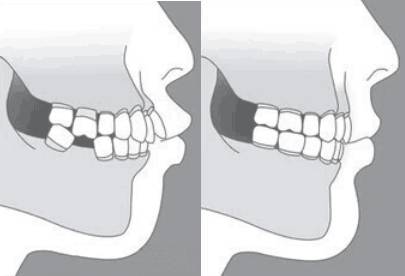

缺牙、松动影响正常的咀嚼

牙缺失会导致相对应位置的上牙松动、脱落不过也不用担心,种植后牙齿恢复咬合关系,面部线条看起来也会自然很多哦!

龅牙是东方人种中为常见的一类牙颌面畸形,在医学专业上实质是上颌前突畸形或双颌前突畸形,一般不伴有严重的功能障碍,但影响美观。龅牙患者常常表现为开唇露齿,自然状态下双唇不能闭拢,微笑时牙龈外露过多,常常伴有颏后缩,强迫闭口时,下唇下方与颏部之间有的软组织隆起。口内上下前牙唇倾,常伴拥挤不齐,前牙深覆牙合、深覆盖。做龅牙矫正费用汇总:10170-20340元